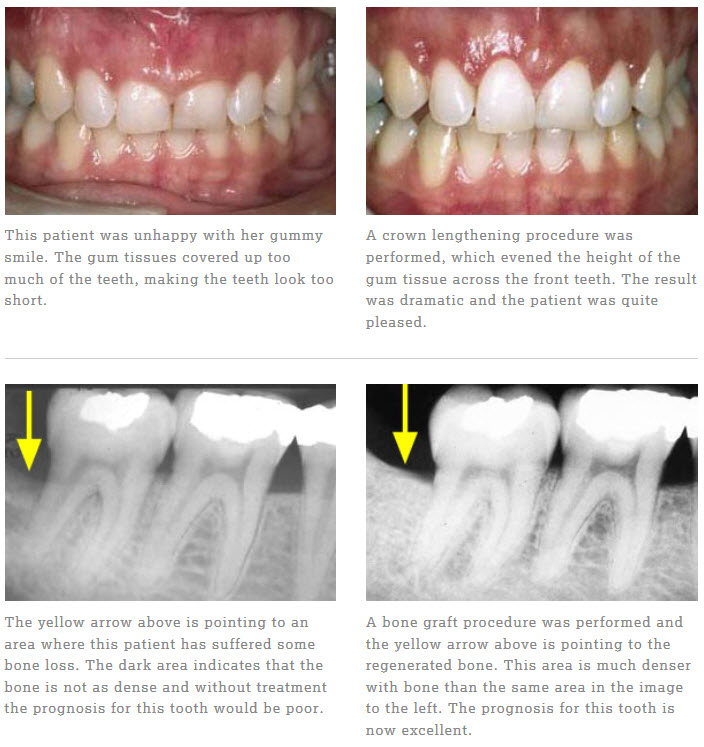

Welcome to our Smile Gallery. We have provided before and after images of examples of procedures we routinely perform in our office. Please click on the links to the left to go directly to a specific procedure section of the gallery to see the results. We work closely with our patients to provide the right solution to create a ‘healthy smile’ that will last a life time.